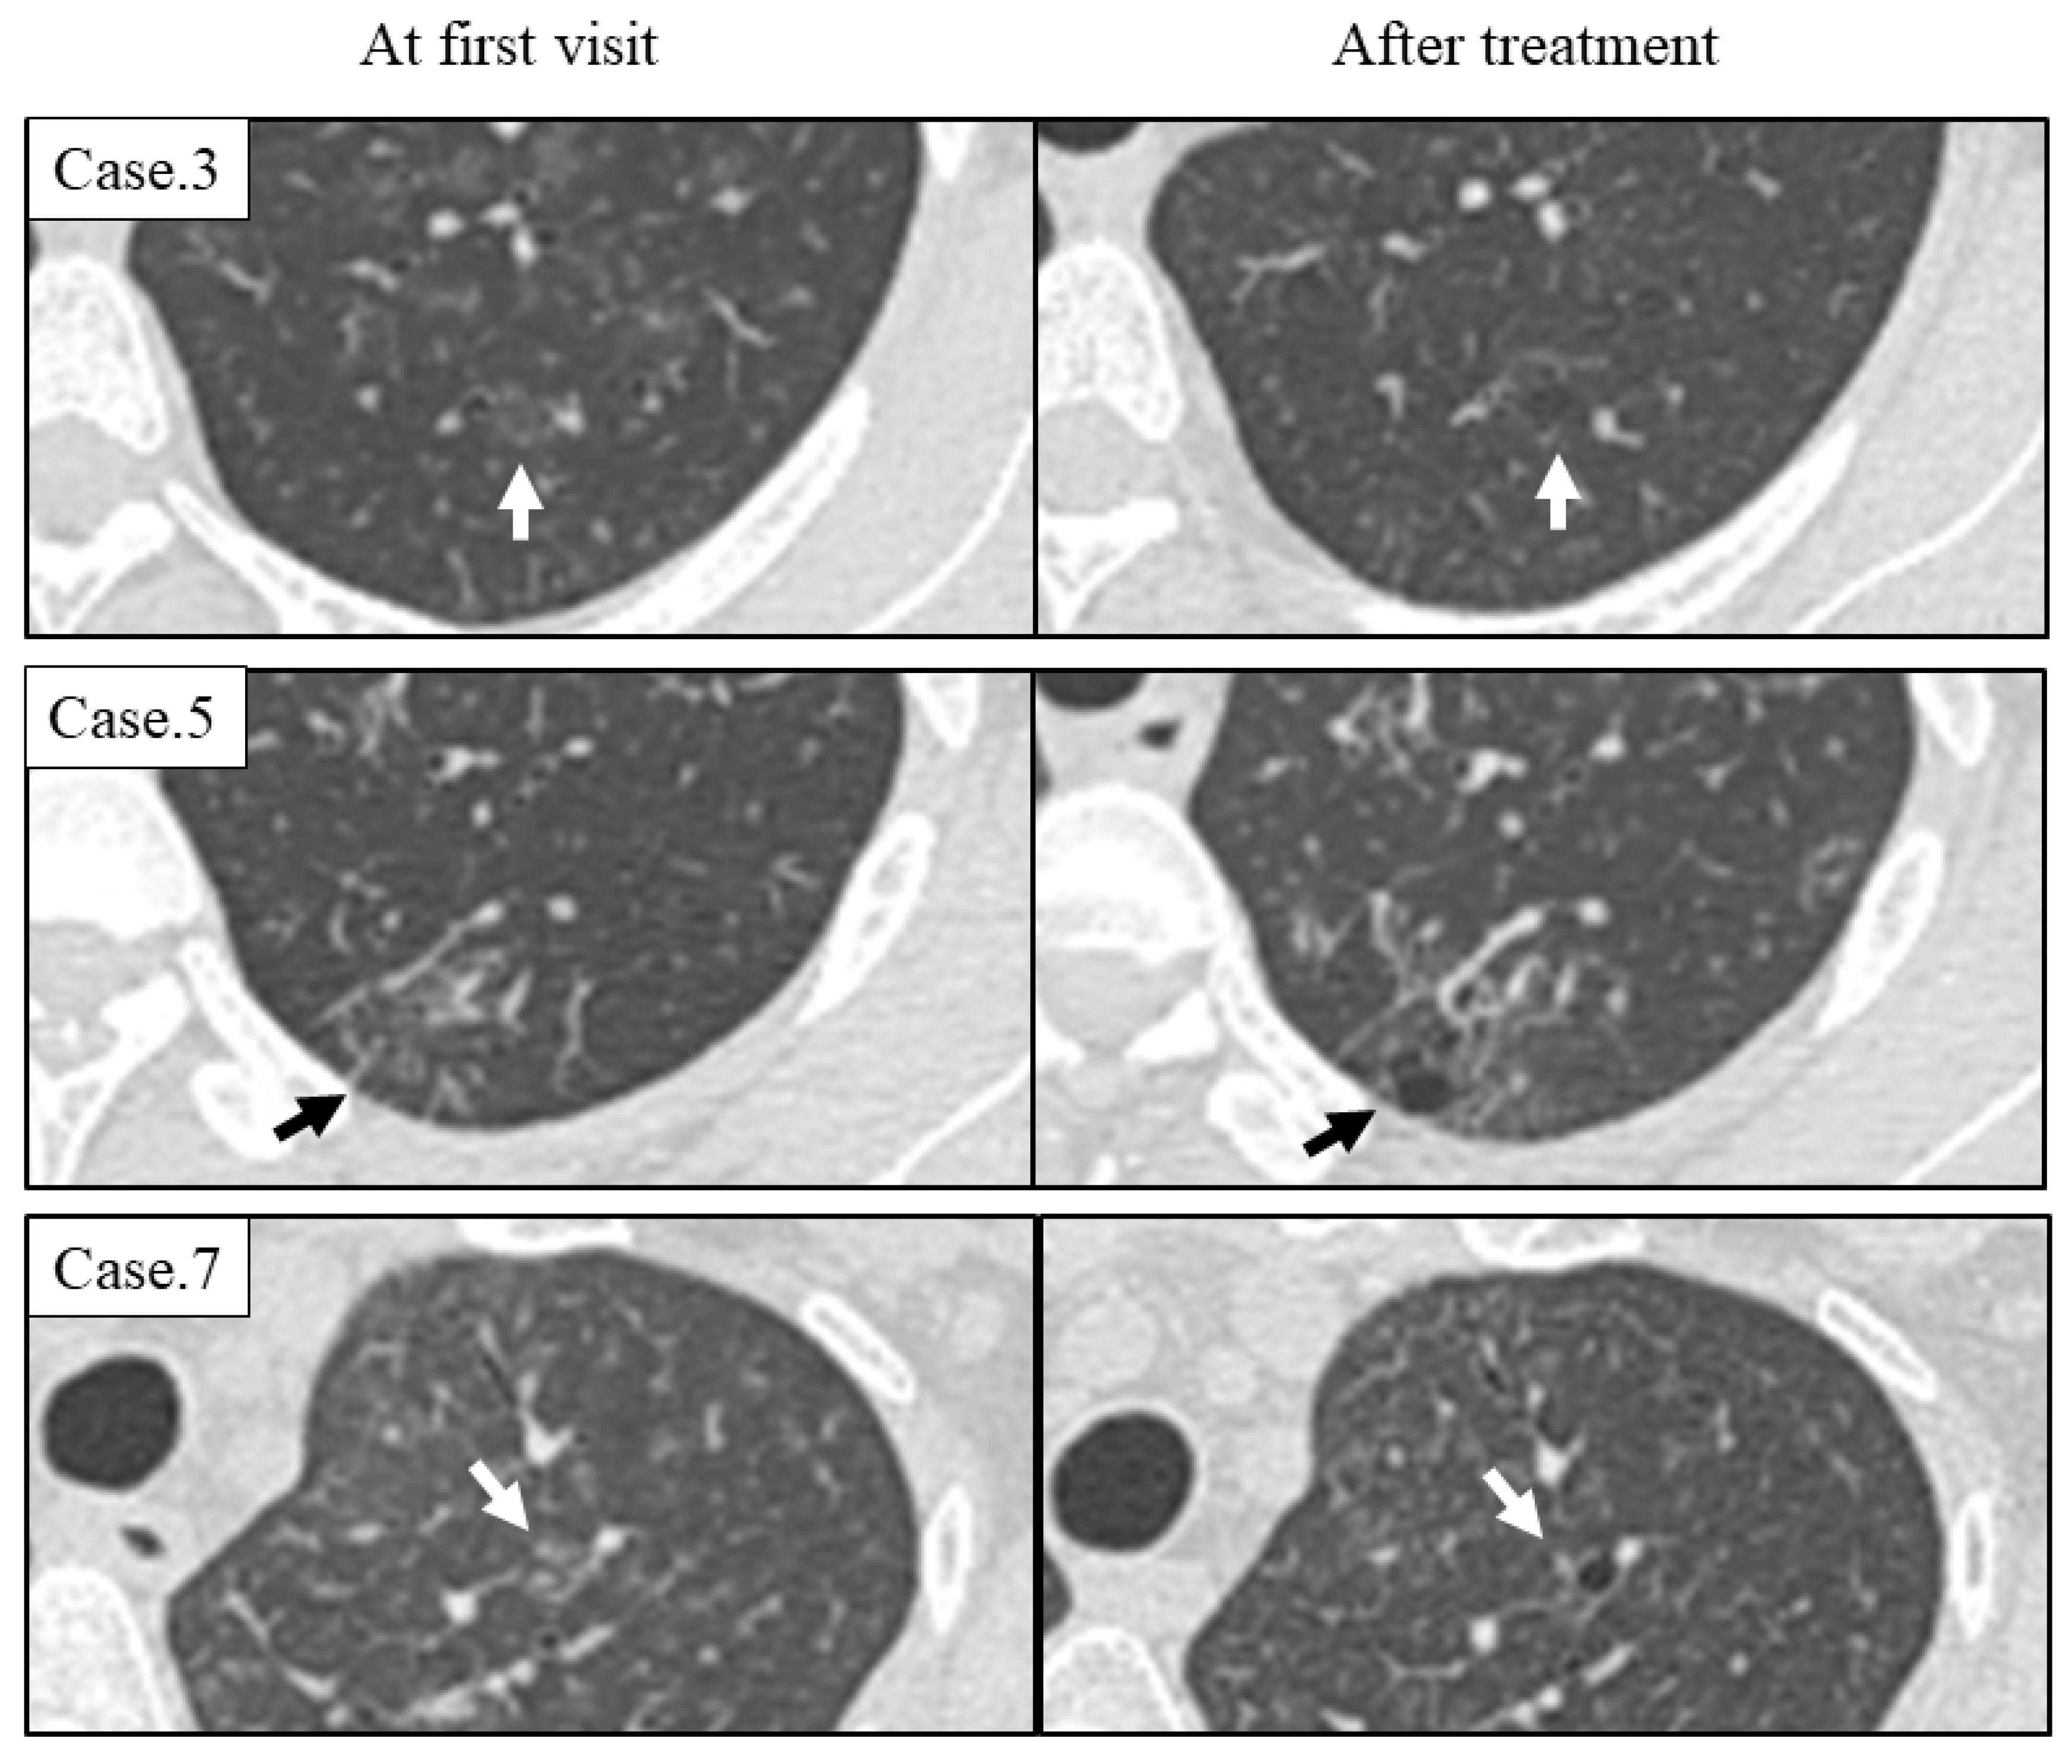

- Pulmonary cysts in idiopathic Castleman disease (MCD) emerged from the area of ground-glass attenuation (GGA) on HRCT, and the cysts did not regress by treatment.

| 3 | + | 25 | 2–10 mm | <2 mm | + | Upper | Interstitial area | TCZ | Increase |

| 4 | + | 12 | 2–8 mm | <2 mm | + | Upper | Interstitial area | PSL + TCZ | Increase |

| 5 | + | 14 | 3–8 mm | <2 mm | + | Upper | Interstitial area | Observation | Increase |

| 7 | + | 3 | 2–3 mm | <2 mm | + | Upper | Interstitial area | TCZ | Increase |